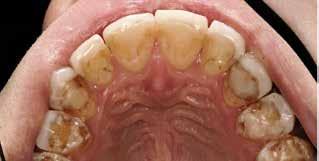

Klinisk undersøgelse viste emaljehypoplasier og hypomineralisering på 1+, +1, 2-, 1-, -1 og -2 (Fig.1). Hun havde Angle klasse II, pladsmangel i begge kæber og agenesi af -5. Der var isninger ved spisning og tandbørstning. Fundene var forenelige

BAGGRUND – Denne kasuistik beskriver en patient, hvor der blev valgt protetisk behandling i ung alder.

PATIENTTILFÆLDE – En niårig pige havde stort behandlingsbehov og smerter fra tænderne på grund af tandudviklingsforstyrrelse. Der var flere gange forsøgt restaurering med komposit, som ikke fungerede. Laminater i feldspatkeram blev valgt for at fjerne mindst mulig tandsubstans, øge holdbarheden på restaureringerne og forbedre æstetikken. Patientens motivation, meninger og kooperationsevne var vigtige for behandlingsvalget, da behandlingen var tidkrævende og til tider udmattende for en ung patient.

KONKLUSION – Resultatet var vellykket og medførte forbedret livskvalitet. Protetisk behandling med adhæsiv teknik kan være et godt behandlingsalternativ for børn og unge på ret indikation.